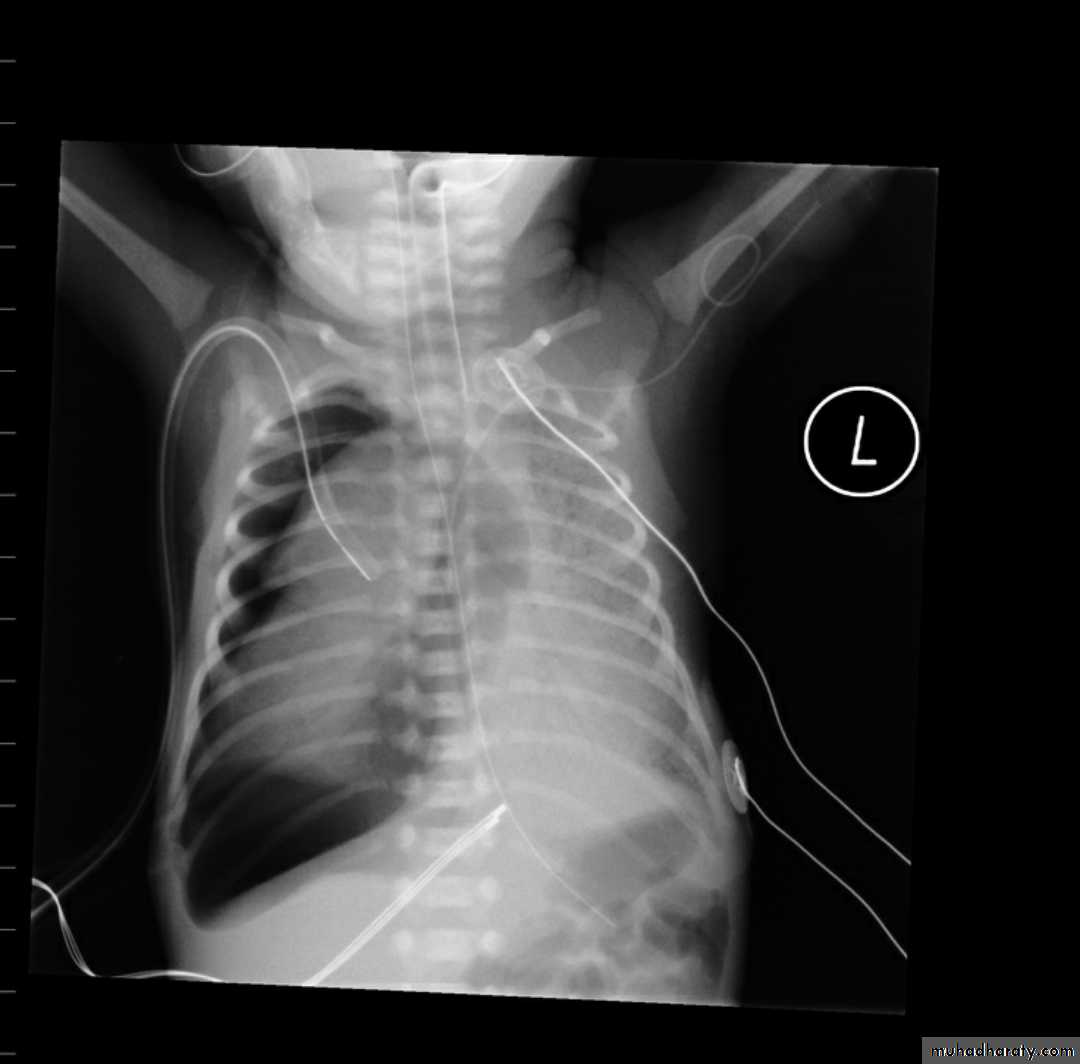

79. Diaphragmatic hernia Vs congenital cystic adenomatous malformation